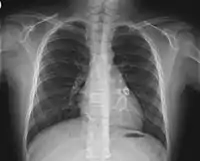

![]() Ураження коронарних судин при синдромі Кавасакі — в тіні серця видно світлі аневризми Ураження коронарних судин при синдромі Кавасакі — в тіні серця видно світлі аневризми | |